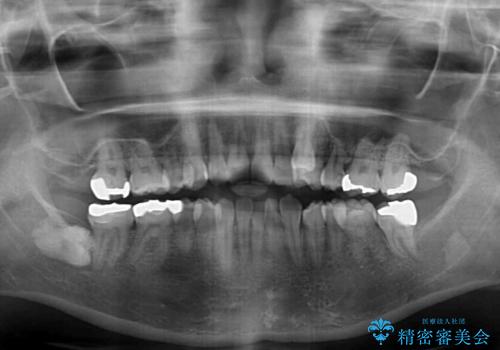

- 左上の八重歯と前歯のデコボコを気にして来院された患者様です。

下顎が左側にズレており、下顎前歯は1歯欠損していたため、左上小臼歯1本を抜歯し、ワイヤー装置にて矯正治療を行うこととしました。